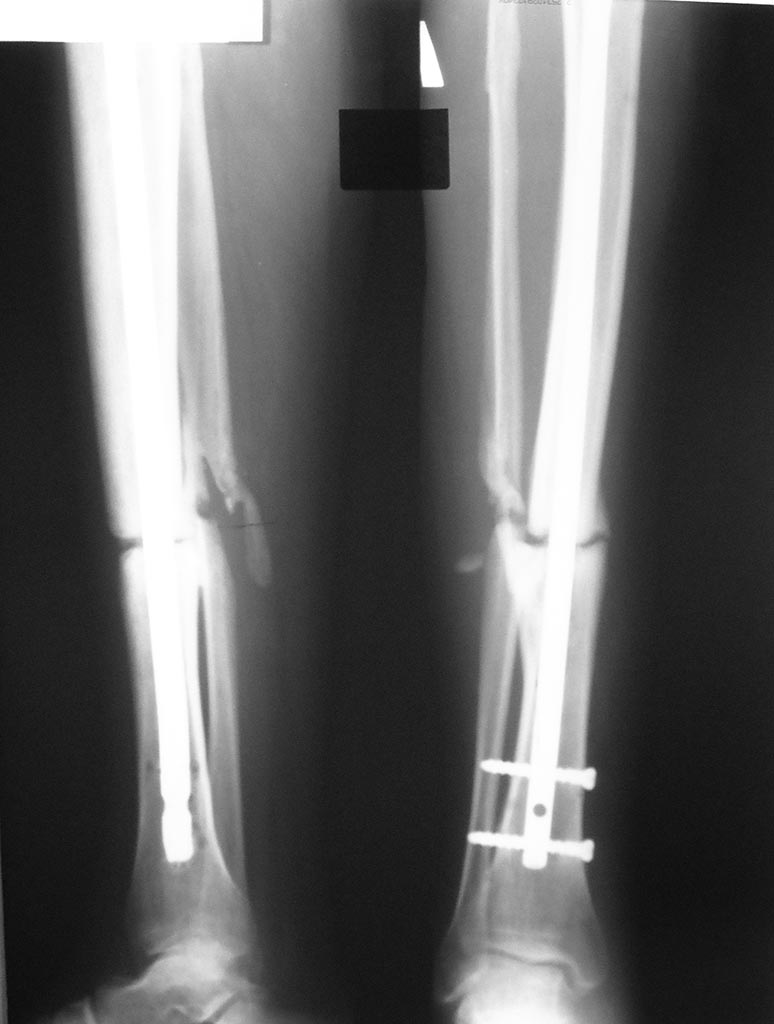

Несращение большеберцовой кости

В январе 2013 г упал с высоты на производстве. В январе-феврале выполнен остеосинтез бедра и обеих голеней.

В настоящий момент хожу с полной опорой на ноги, боли после длительной физической нагрузки. На контрольной Р-грамме несращение голени слева. Предлагают две операции - первая удаление штифта и шурупов, поставить пластину с донорской костью из таза. Вторая - удалить нижние винты. Но я беспокоюсь, что штифт пробъёт кость. Что посоветуете.

Вообще, если к полугоду нет сращения, надо делать реостеосинтез с рассверливанием. То есть менять стержень на больший по диаметру. Ничего из таза брать не надо. Вариант с пластиной - более трудоемкий, длительный и рискованный. Есть и много других вариантов.